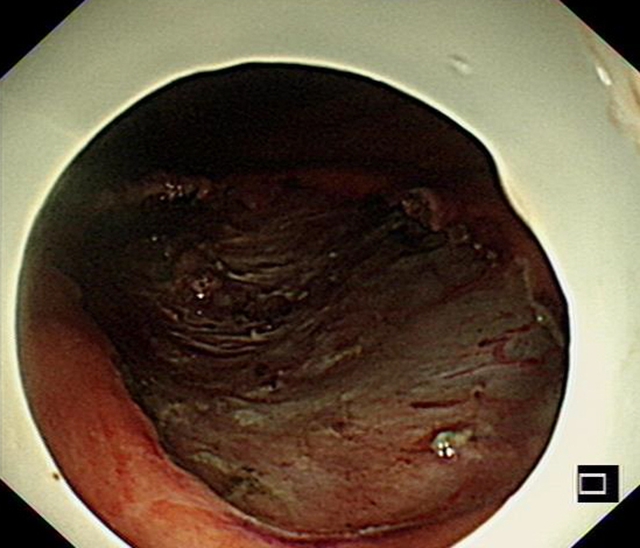

目前,李婆婆饮食恢复正常,无腹痛、腹胀等症状,“与一开始见到的她简直像两个人,在近日的胃镜复查中,她的胃壁已完成愈合,并没有肿瘤的复发”汤小伟副教授说。

术后4月后,患者复查胃镜提示胃内创面已经完全痊愈,肿瘤没有复发。